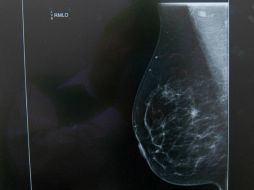

Tecnología Analizan nuevas técnicas para mejorar resultados de imágenes médicas 6 de enero de 2016 - 16:17 hs Cáncer Investigación científica

Suplementos Implantes de seno no provocan cáncer de mama 8 de agosto de 2015 - 13:56 hs Cáncer de mama Calor de hogar